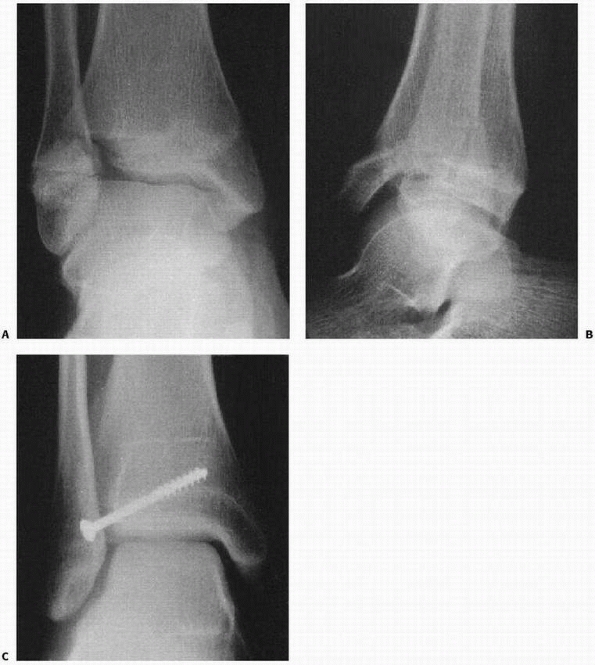

![]() |

FIGURE 26-35 A.

Severe ankle injury sustained by an 8-year-old involved in a car accident. The anteroposterior view in the splint does not clearly show the Salter-Harris type IV fracture of the tibia. The dome of the talus appears abnormal. B. CT scan shows the displaced Salter-Harris type IV fracture of the medial malleolus and a severe displaced intra-articular fracture of the body of the talus. C,D. Open reduction of both fractures was performed, and Herbert screws were used for internal fixation. (Courtesy of Armen Kelikian, MD.) |